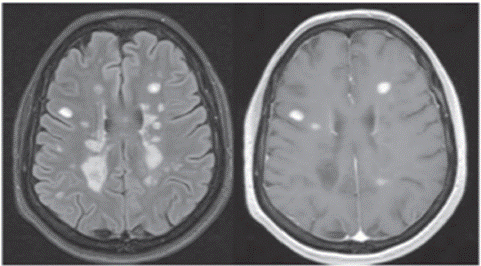

A brain MRI was performed to rule out other etiologies causing the current symptoms, which only evidenced periventricular hyperintense lesions suggestive of demyelination, compatible with multiple sclerosis (Figure 1). It was considered to be of relapsing-remitting type, due to time of evolution and diagnosis.